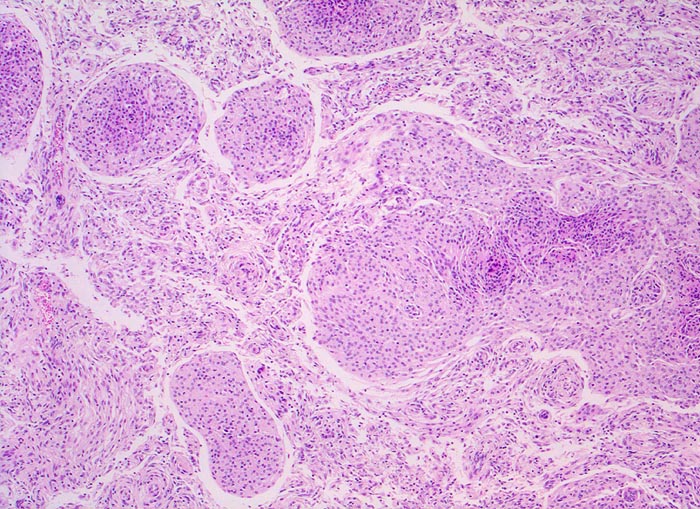

Das Meningeom zeigt ein grosses Spektrum histologischer Varianten mit sehr unterschiedlicher Morphologie. Am häufigsten sind meningotheliale (ihr Präparat), transitionale und fibroblastische Meningeome. Typisch für das meningotheliale Meningeom sind dicht gepackte Zellen mit unscharfen Zytoplasmagrenzen, Wirbelbildungen und Kerne mit intranukleären Vakuolen. Ferner finden sich konzentrische Verkalkungen in Form von Psammomkörperchen (> 255).

Morphologische Merkmale:

• Der Dura breitbasig aufsitzender scharf begrenzter halbkugeliger Tumor.

• Kugelige Tumorzellverbände mit Ausbildung von typischen konzentrischen zwiebelschalenartigen Formationen und parallele Bündel spindeliger Zellen.

• Tumorzellen mit ovalen Kernen ohne Atypien und reichlich Zytoplasma. Keine Mitosen.

• Psammomkörperchen (konzentrisch geschichtete Verkalkungen).